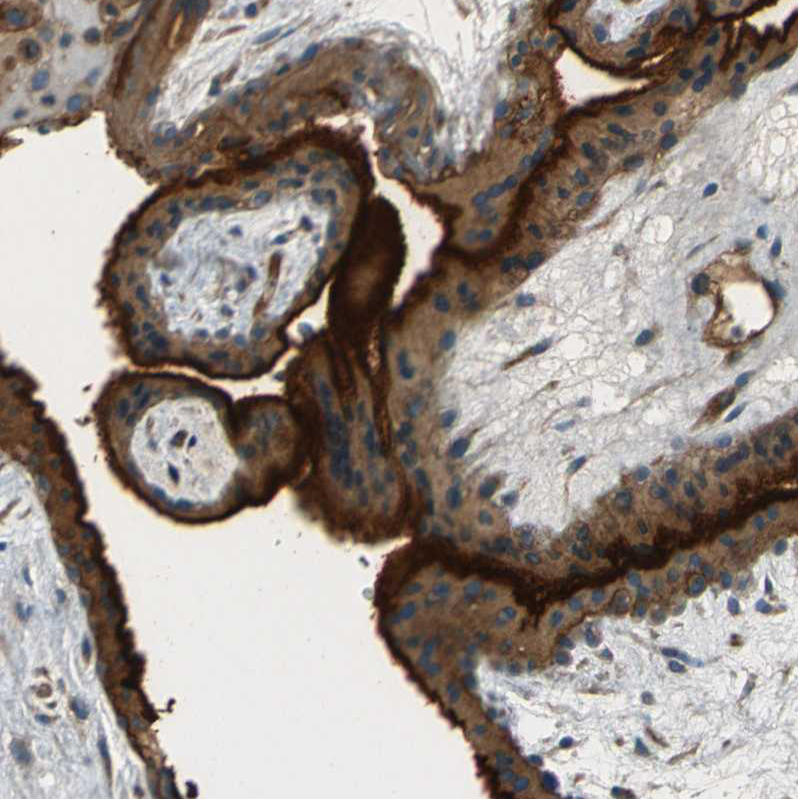

Immunohistochemistry analysis in human placenta and skeletal muscle tissues using HPA014067 antibody. Corresponding ENTPD1 RNA-seq data are presented for the same tissues.